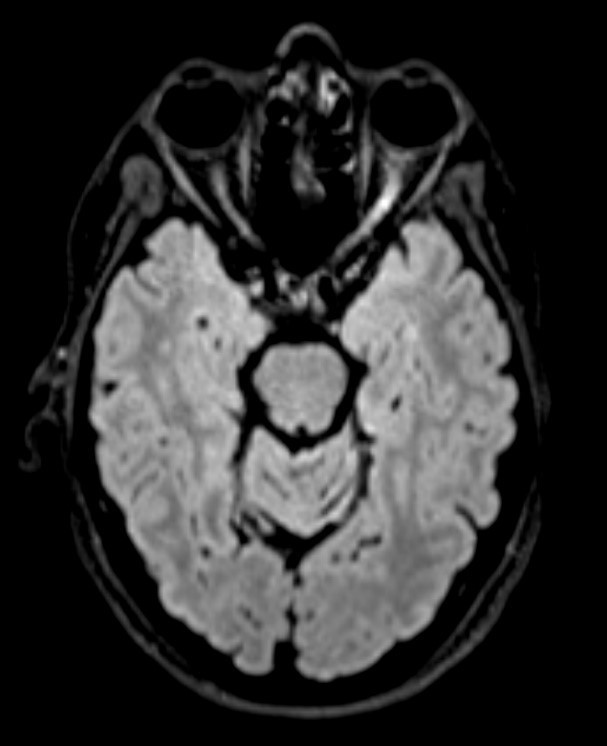

Dissémination spatiale : plusieurs territoires atteints cliniquement, au moins deux territoires atteints en IRM parmi : le territoire périventriculaire, le trajet des nerfs optiques, la région sous/juxta- et intracorticale, la fosse postérieure, la moelle épinière. Particularité des nouveaux critères : prendre en compte les lésions de la fosse postérieure et de la moelle symptomatiques.

Dissémination temporelle : plusieurs poussées cliniques dans le temps, apparition de nouvelles lésions entre les IRM, ou certaines lésions prennent le contraste et pas d’autres sur une même IRM, ou apparition d’une synthèse intrathécale dans le LCS.